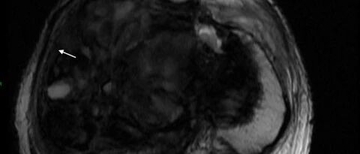

• MRI研究伴中央颞区棘波儿童自限性癫痫语言功能进展